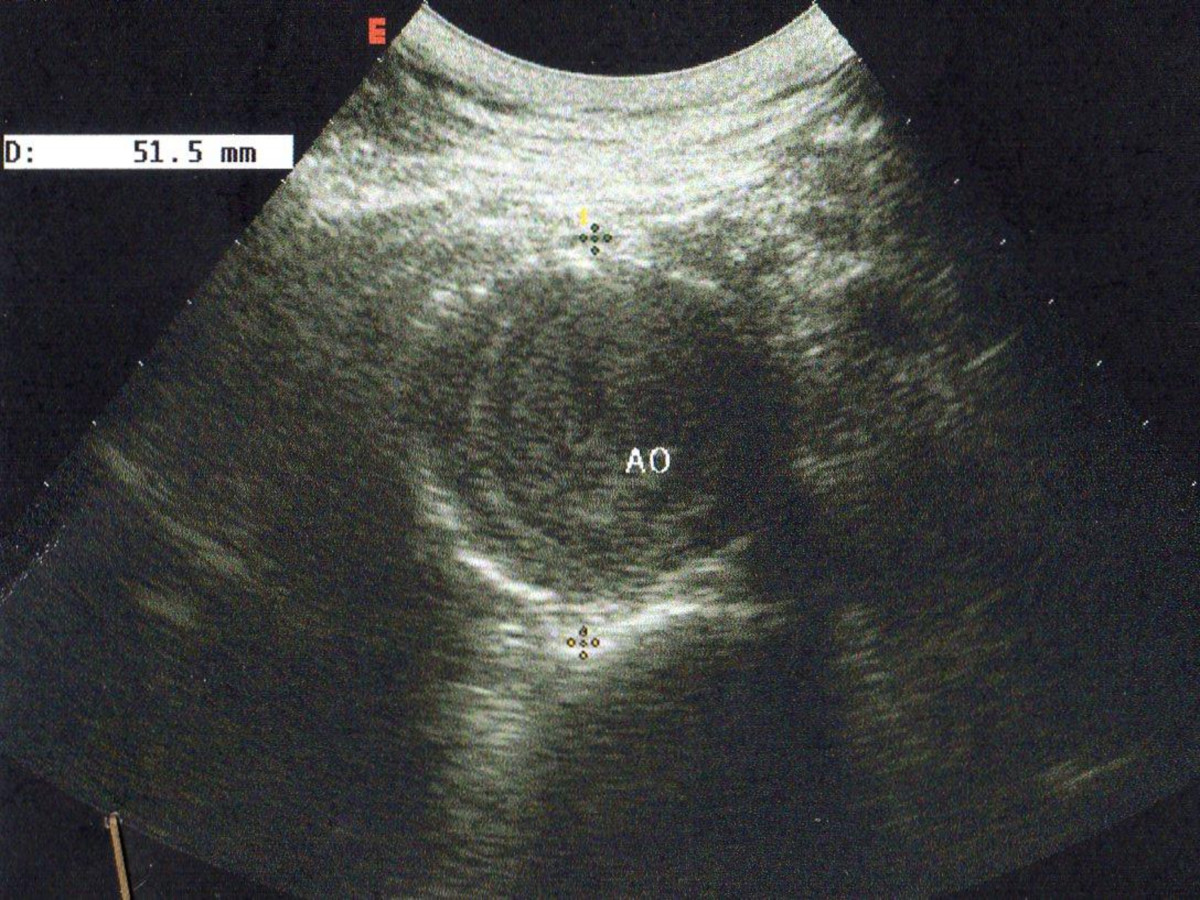

Endovascular repair of anastomotic abdominal aortic aneurysm, after aortobifemoral bypass

Vascular Clinic, Naval and Veterans Hospital of Athens

AVEM2009-Thessaloniki